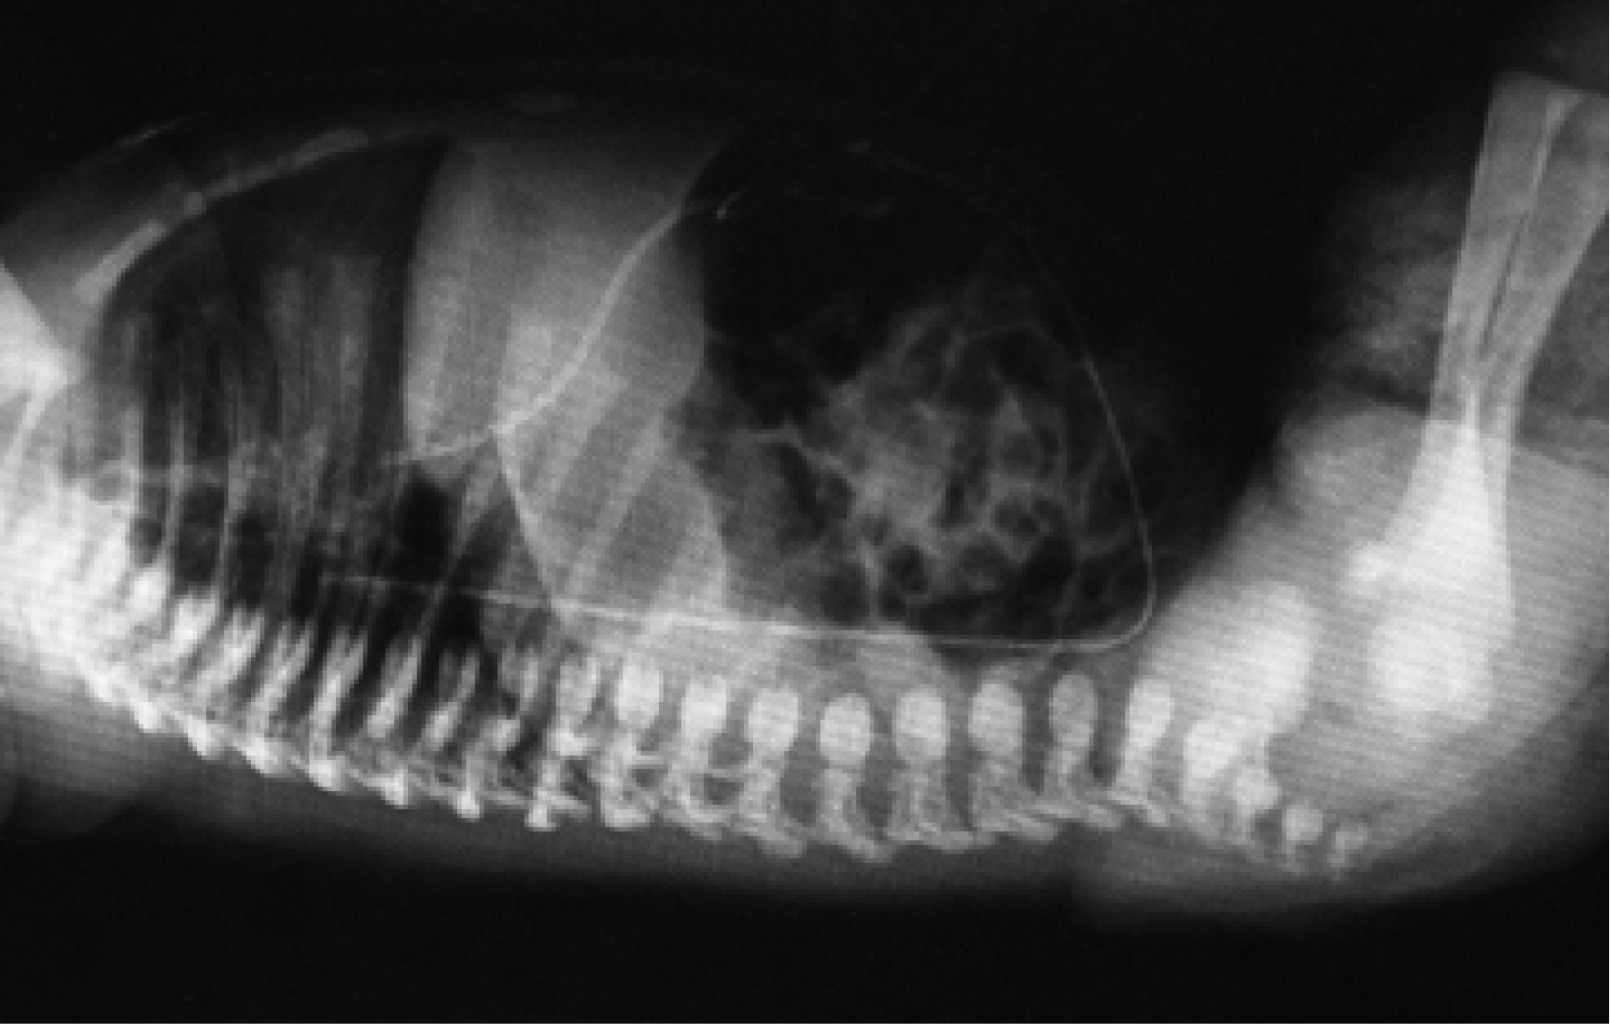

Catéter arterial. La punta del catéter arterial tiene dos posiciones correctas: alta y baja. La posición alta radiológicamente debe quedar entre las vértebras (dorsales o torácicas) D6-9; mientras que la baja entre las vértebras (lumbares) L3-4. De esta manera, se evita la zona peligrosa que queda en el espacio comprendido entre la vértebra dorsal 10 y la vértebra lumbar 2. Esta zona peligrosa comprende el nacimiento de grandes troncos arteriales (tronco celíaco situado en D11, arteria mesentérica superior en D12-L1, arteria renal izquierda y derecha en L1-L2, arterias vertebrales dorsales y lumbares, arteria mesentérica inferior en L3 y bifurcación de la aorta en L4) que deben ser evitados por la posibilidad de provocar la liberación de émbolos o momentos de isquemia que condicionen la aparición de daño renal, intestinal, de médula espinal o de extremidades inferiores (Figuras 7 y 8).2

Una vez conocida la distancia hombro-ombligo, recurrimos al nomograma de Dunn arterial (Figura 3), y seleccionamos en las abscisas esta distancia, enseguida determinamos la altura del catéter, alta o baja. Si seleccionamos la posición alta, situamos la punta del catéter en la mitad de las líneas que delimitan ombligo-diafragma y ombligo-válvula aórtica, y de esta manera se obtiene en las ordenadas la distancia a introducir del catéter arterial alto. Si deseamos colocar la punta del catéter arterial en posición baja, seleccionamos la distancia hombro-ombligo en las abscisas del monograma de Dunn arterial y la punta del catéter lo situamos inmediatamente por arriba de la línea ombligo-bifurcación de la aorta y, de esta manera, determinamos en las ordenadas la distancia a introducir del catéter arterial bajo. Siempre debemos sumar la longitud del muñón umbilical a la distancia obtenida. Antes de fijar y retirar campos estériles solicitamos una radiografía toracoabdominal portátil para determinar la posición de la punta del catéter y si es necesario se hacen modificaciones. Una vez terminado el procedimiento de colocación y posicionamiento del catéter arterial umbilical y de haber retirado el campo estéril no será posible introducir el catéter para tratar de dejar la punta en posición correcta, pero sí se podrá retirar algunos centímetros para posicionarlo correctamente. El trayecto que normalmente debe seguir el catéter arterial es el siguiente: se introduce por una de las arterias umbilicales, derecha o izquierda, deslizándose por la arteria hipogástrica, derecha o izquierda, llegando a la arteria iliaca interna, derecha o izquierda, continuando por la arteria iliaca, derecha o izquierda, y llegar a la arteria aorta para ascender a una posición correcta baja entre las vértebras L3-4 o alta entre las vértebras D6-9 (Figuras 4 y 9).

• 2. Se pueden diferenciar radiológicamente por su trayecto anatómico, el catéter venoso al entrar a pared abdominal se dirige hacia dirección cefálica y se sitúa en el lado derecho de abdomen y el arterial al entrar a pared abdominal se dirige hacia dirección podálica, de tal forma que baja para entrar a la arteria iliaca interna derecha o izquierda y hace un bucle para ascender por las iliacas y llegar a la arteria aorta, situándose ligeramente por el lado izquierdo del abdomen.

• 6. En una radiografía tangencial de abdomen y tórax, los catéteres tienen una distribución muy particular, el venoso se dirige siempre hacia dirección cefálica, hacia arriba por la pared abdominal anterior para pasar a un lado del hígado y llegar al corazón derecho. El catéter arterial se dirige siempre hacia dirección podálica, hacia abajo de la pared abdominal hasta alcanzar la arteria iliaca interna derecha o izquierda y de esta forma ascender para llegar a la arteria aorta, haciendo un bucle y correr por encima de los cuerpos vertebrales lumbares y dorsales (Figuras 12 y 13).